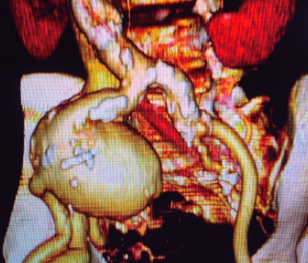

Oliver Daniel Maida Medina, Xavier Ander De Aretxabala Urquiza, Giancarlo Schiappacasse Faúndes, Leonor Adriana Castiblanco Galvis

|